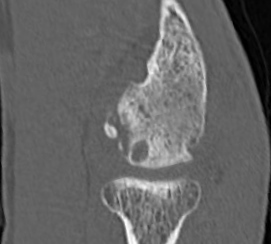

CT画像①

上腕骨小頭に骨欠損

②

上腕骨小頭に遊離体

③

同じく遊離体